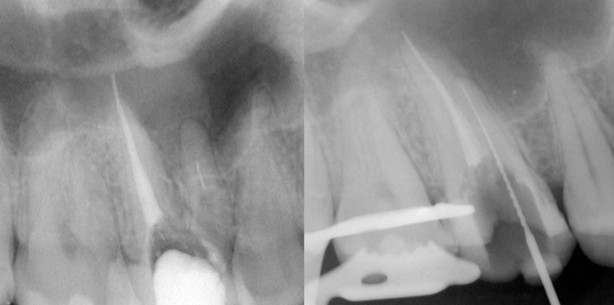

Nach erfolgter Information über die vermutete Prognose unternehmen wir den Versuch, das frakturierte Instrument darzustellen. Nach Entfernung der Aufbaufüllung werden die Kanaleingänge dargestellt (Abb. 2). Es zeigt sich, dass neben dem distovestibulären Kanal auch ein vierter Kanal (mb2) vorhanden ist. Die Darstellung der Wurzelkanaleingänge erfolgt in unserem Haus mit dem Aufsatz 1R des Tigon+. Dank der Abwinkelung des Instruments profitiert man von einer sehr guten Sicht auf die Behandlungsstelle. Zudem erlaubt es ein schnelles und gezieltes Abtragen von Dentin, ohne dabei den Zahn unnötig zu schwächen.

Nach Darstellung aller Wurzelkanaleingänge wird in einem zweiten Schritt das frakturierte Wurzelkanalinstrument dargestellt (Abb. 3 und 4). Hierfür verwenden wir den Aufsatz 3E des Tigon+. Durch die schmale und lange Form des Instruments erreichen wir einen tiefen und schmalen Zugang. Sofern es sich um ein kleines Frakturstück handelt, kann es durch aktive Übertragung von Energie des Ultraschalls zu einer Lockerung des Fragments kommen. Lockert es sich nicht, so „umkreist“ man das Instrument vorsichtig, um es anschließend mit einer Spritze gefüllt mit Palavit G zu greifen, zu fixieren und zu entfernen (Abb. 5). Nach Entfernung des Instruments erfolgt eine Kontrollaufnahme (Abb. 6). Hat man diesen Punkt erreicht, muss man sich nun Gedanken über die Wurzel kanalreinigung machen. Hier wird Ultraschall zum Ak tivieren von Spülflüssigkeiten im Wurzel kanalsystem eingesetzt. Dabei schwingt die Ultraschallspitze frei im Kanalkonus und aktiviert die umliegende Spülflüssigkeit (Aufsatz 1E). Die Desinfektionswirkung der Spüllösung hängt von mehreren Faktoren (wie z.B. Temperatur, Konzentration und Einwirkzeit) ab. Eine einfache Methode, die Wirksamkeit wesentlich zu erhöhen, ist die Ultraschallaktivierung.